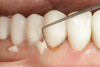

Fig 6. A bioactive cavity liner (TheraCalTM LC, Bisco Dental Products) is placed then cured on the affected dentin to the edge of the matrix because there is little to no enamel at the cavosurface margin of the preparation.

Figure 6